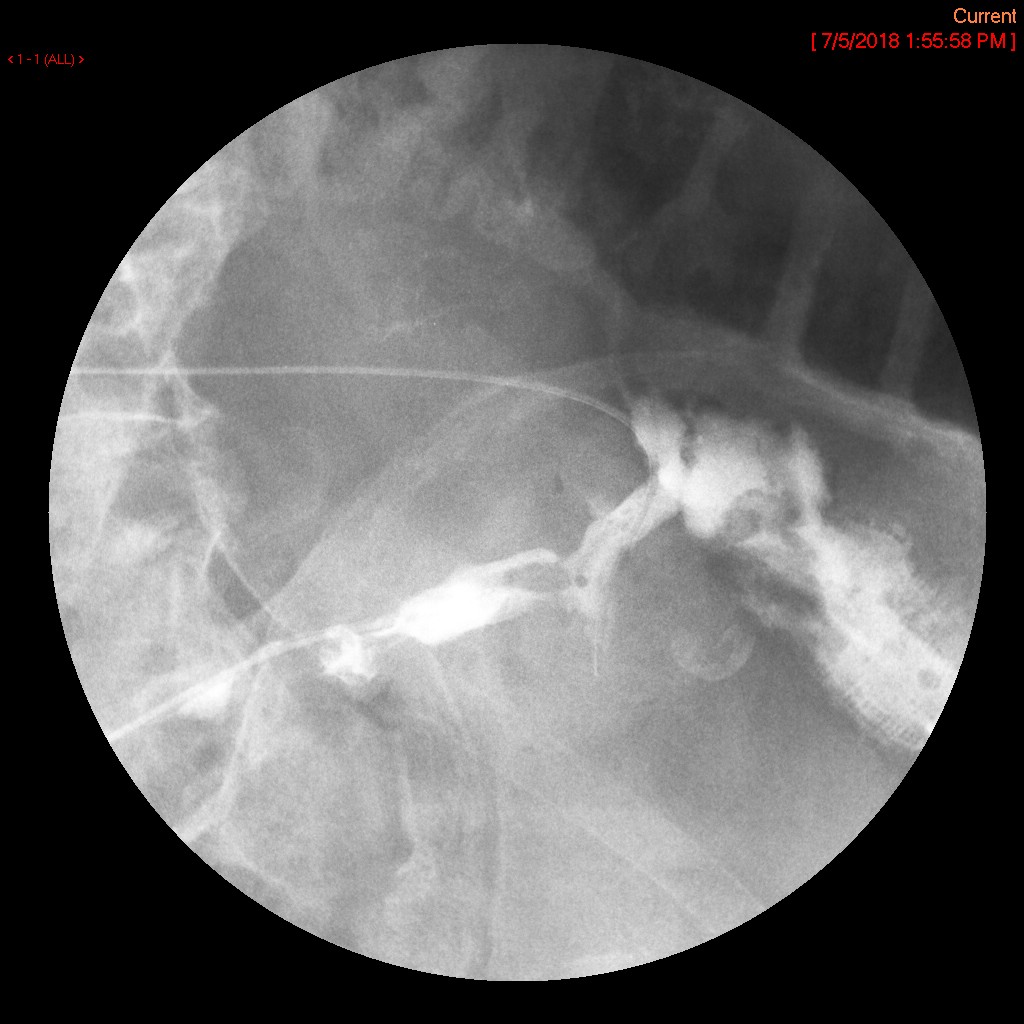

- Upon entering the room, the patient will already be positioned supine on the fluoroscopy table. The interventional portion of the exam is performed by the Gynecology Department; the cervix should be cannulated and a catheter placed when you enter the room.

- The gynecologist will begin injecting contrast material into the uterus. Obtain images periodically throughout the procedure (usually at the direction of the gynecologist). The images should include the uterine cavity filled with contrast material, bilateral fallopian tubes filled with contrast material, and spillage and dispersion of contrast material into the peritoneal cavity (image 1) (image 2) (image 3) (image 4) (image 5).

- It may be necessary to place the patient into either the right lateral or left lateral oblique postion to define the anatomy more clearly.

- Spillage into the peritoneal cavity is not always seen. If this occurs during the examination, be sure to note it in the dictation.